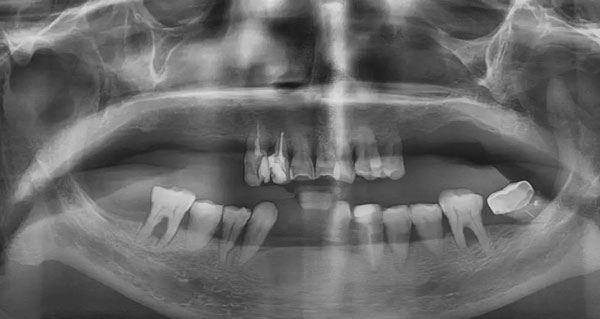

邓女士种牙前全景片

多颗牙缺失+牙周病

让她嘴角干瘪,前牙外凸,严重影响面型